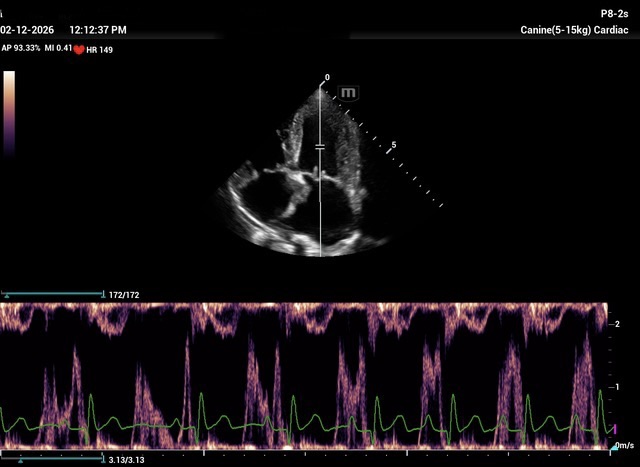

Chronic stage C MVD.TID Pimo and Lasix(high dose), ACEi and Spirono. Doing well. Recheck: Idexx GHP= CBC-NSF ,SDMA 15,BUN 14.1mmol/L, Creat 79umol/L. US: Cornell Indx LVd=1.46(prev2.1), LV septal flattening with diastolic dip,LAAO=2.47,Evel1.45m/s, TVregPG-68mmHg,HV distension-mod ascites.LV and LA underloading via diuretics and PHT (mild PHT past).PHT more pre vs post cap based on small LVsize? Consider Sildenafil/L Arg.Concerned about developing L CHF.Is CHF less likely adding PDE5i with MVD/PHT in underloaded LV than same scenario with vol overloaded LV at similar staging. MVPG=120.3mmHg

My bad! The TV regurge CW Jpeg submitted was mislabeled as MV E vel and its pressure gradient. Sorry for any confucion.

Thanks. Not sure if any sig. MV stenosis?? My experience limited.3 PWD from diff times. Ls7 vid. is from 2024,initially thinking reverse remodelling where the lasix lowering preload and Pimo is decreasing LV size via decreased resist/increase cxn while LA no change because it’s a chronic filled remodeled saggy bag receiving Regurge volume??